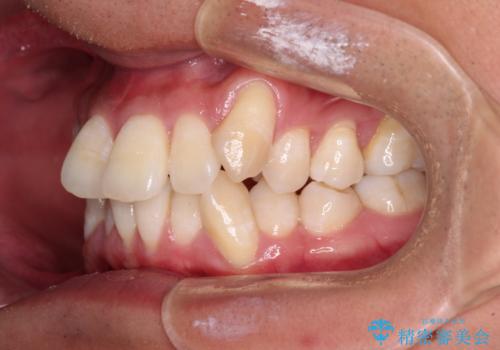

- 八重歯と飛び出している前歯を気にして来院された患者様です。

歯列としてはインビザラインでもワイヤー矯正でも対応できるものでしたが、上顎の八重歯や下顎小臼歯の捻転といったインビザラインでは時間のかかってしまう歯列不正が認められたため、補助装置やワイヤー矯正を治療当初に使用することで、インビザラインによる治療をスムーズに行えるように計画しました。